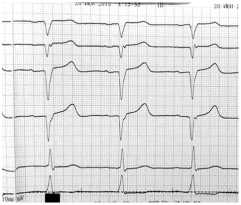

В течение последующих 4 лет записей в амбулаторной карте нет. В 2012 году обратилась в поликлинику с жалобами на дискомфорт в области сердца. Пациентка направлена к кардиологу. Снята ЭКГ и с диагнозом: ИБС: острый инфаркт миокарда (неизвестной давности) пациентка госпитализирована по «скорой помощи» в кардиореанимационное отделение многопрофильного стационара (рис. 1).

Рисунок 1. ЭКГ больного (59 лет)

Таким образом, неадекватный контроль гликемии, применение в течение длительного времени неэффективной схемы сахароснижающей терапии, отсутствие консультации с эндокринологом и зав. отделением (многократные визиты в поликлинику и без результатов), потеря контакта с больной почти на 4 года привели к тому, что развилось одно из грозных осложнений СД – острый инфаркт миокарда.